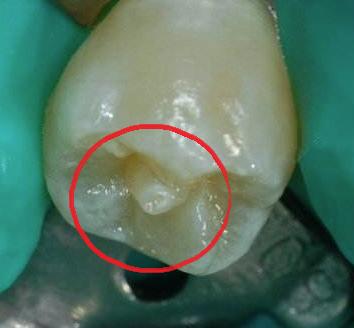

接诊的邵旭媛医生给小杰做了口腔检查后发现,在小杰左下后牙上有一处破损,而对称的右边牙齿上长了一个圆锥形的凸起,就仿佛牙齿上又长了一颗小牙齿。

(网络图)

“这是畸形中央尖,左边的畸形尖已经折断了。”邵医生进一步检查后发现,小杰左下后牙的牙髓已经感染发炎了,这才导致了牙疼。